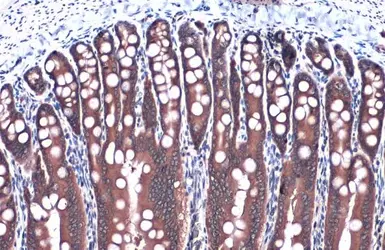

Anti-GAPDH antibody used in IHC (Paraffin sections) (IHC-P). GTX100118

GTX100118 IHC-P Image

GAPDH antibody detects GAPDH protein at cytoplasm by immunohistochemical analysis.

Sample: Paraffin-embedded mouse duodenum.

GAPDH stained by GAPDH antibody (GTX100118) diluted at 1:1000.

Antigen Retrieval: Citrate buffer, pH 6.0, 15 min